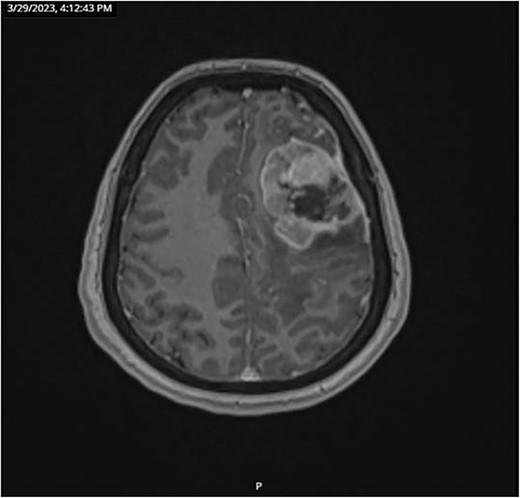

CT and PET scans revealed multiple positive lymph nodes, but metastatic lesions were not found in chest, abdominal organs, or bone (Fig. 2). Genetic and molecular tests revealed wild rat associated sarcoma, wild BRAF, proficient MMR, and negative HER-2. Tumor markers were positive. The patient started chemotherapy, which included CAPOX, cetuximab, and FOLFOX. PET scan was done for re-evaluation, and marked partial disease response was observed with currently no evidence of disease. After that, the patient started to experience reversible amnesia, bizarre behavior followed by right side upper limb weakness, hyperreflexia on the right side, positive Babinski sign on the left, and positive Hoffman sign bilaterally. Brain MRI was done, which revealed a left fronto-parietal extra-axial space-occupying lesion with vasogenic edema and midline shift (Fig. 3). Patient underwent brain lesion resection through left fronto-parietal craniotomy. The pathology revealed GBM (Fig. 4). IHC stain of neoplastic cells showed wild IDH and positive for GFAP, and 30% of the neoplastic cells showed positive for Ki67.

PET scan revealed multiple positive lymph nodes but no metastatic lesions in chest or abdominal organs or bone.